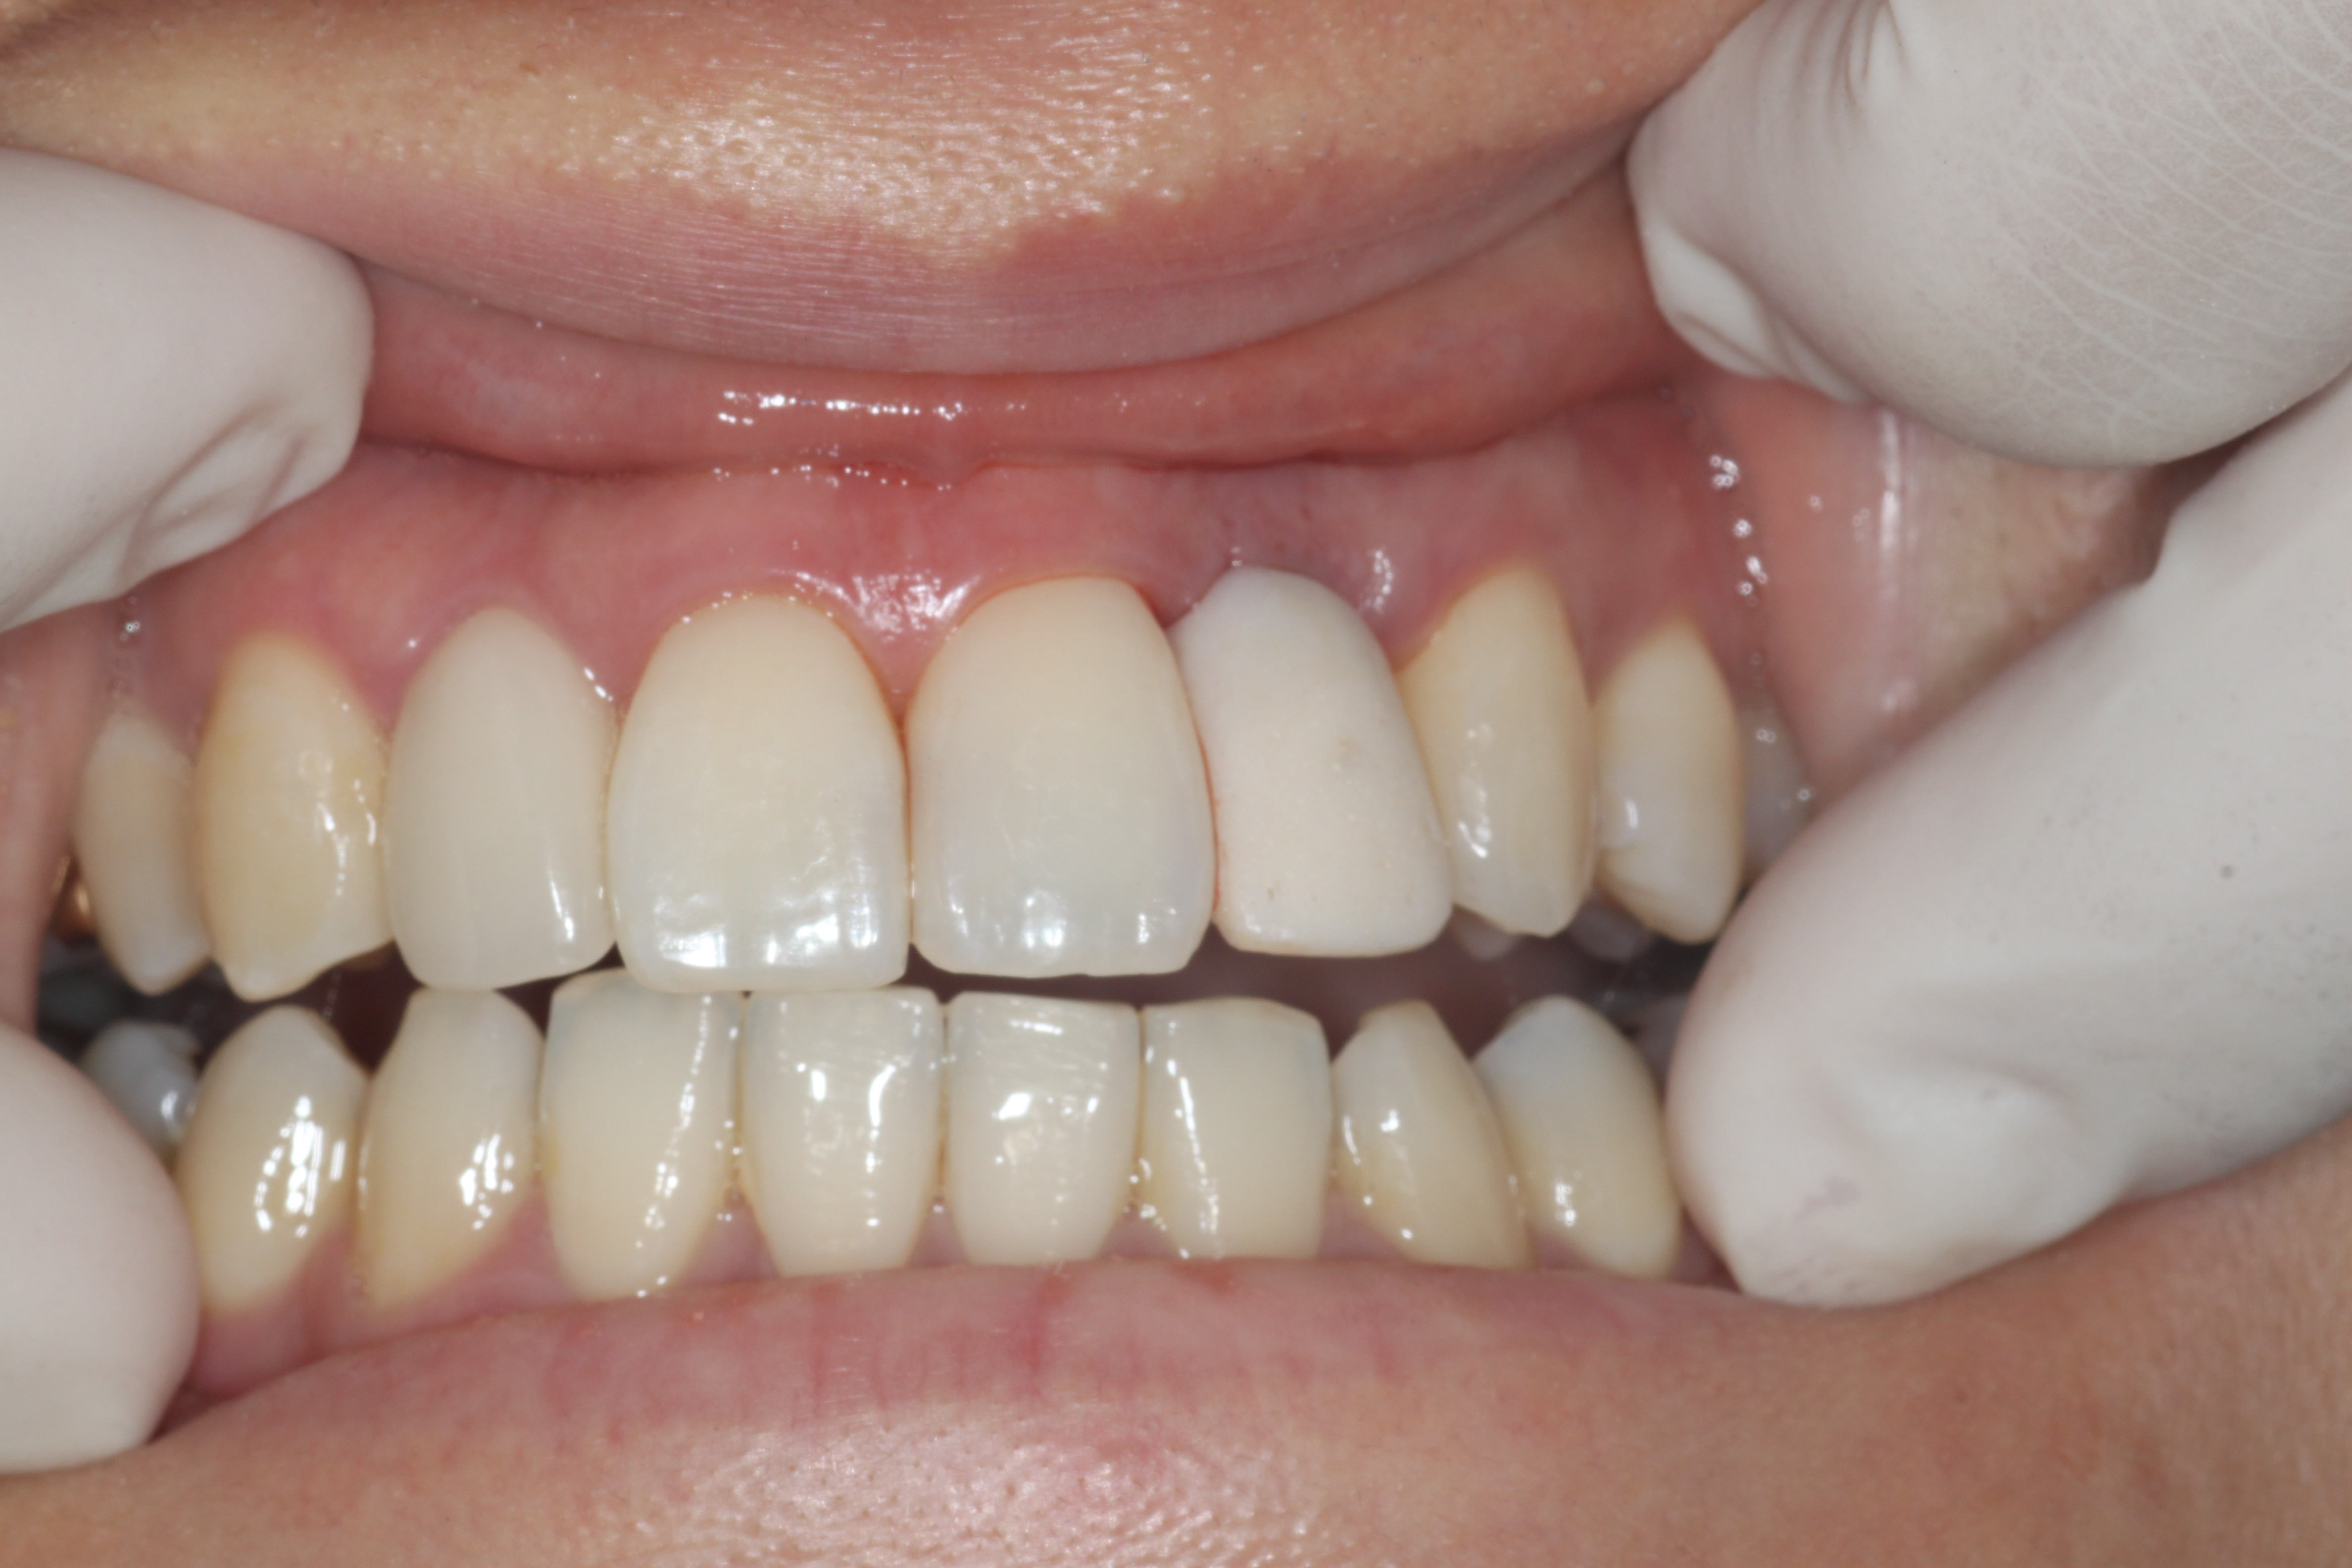

24³â 03 15ÀÏ ÀüÄ¡ºÎ½Ä¸³°í°ú °¡ÀÇÄ¡¸¦ ¸¸µé¾îÁÖ¾úÀ¾´Ï´Ù.

36¼¼¿© ȯÀÚºÐÀÔ´Ï´Ù.1¿ù¿¡ ¸¹ÀÌ Èçµé¸®°í »ÀÀÇ Èí¼ö°¡ ½ÉÇØ °ñÀ̽ĸ¸ ÇØ ³õ°í ÀÕ¸ö°ú °ñÁ¶Á÷À̾î´ÀÁ¤µµ Çü¼ºµÇ¾î ÀÓÇÁ¶õÆ®¸¦ ½Ä¸³ÇÏ¿´À¾´Ï´Ù.